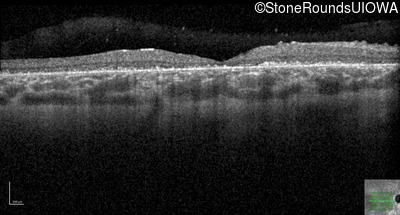

Optical Coherence Tomography - Left - 20/100 -2 sc

Exemplar / OCT Stack

OCT Stack